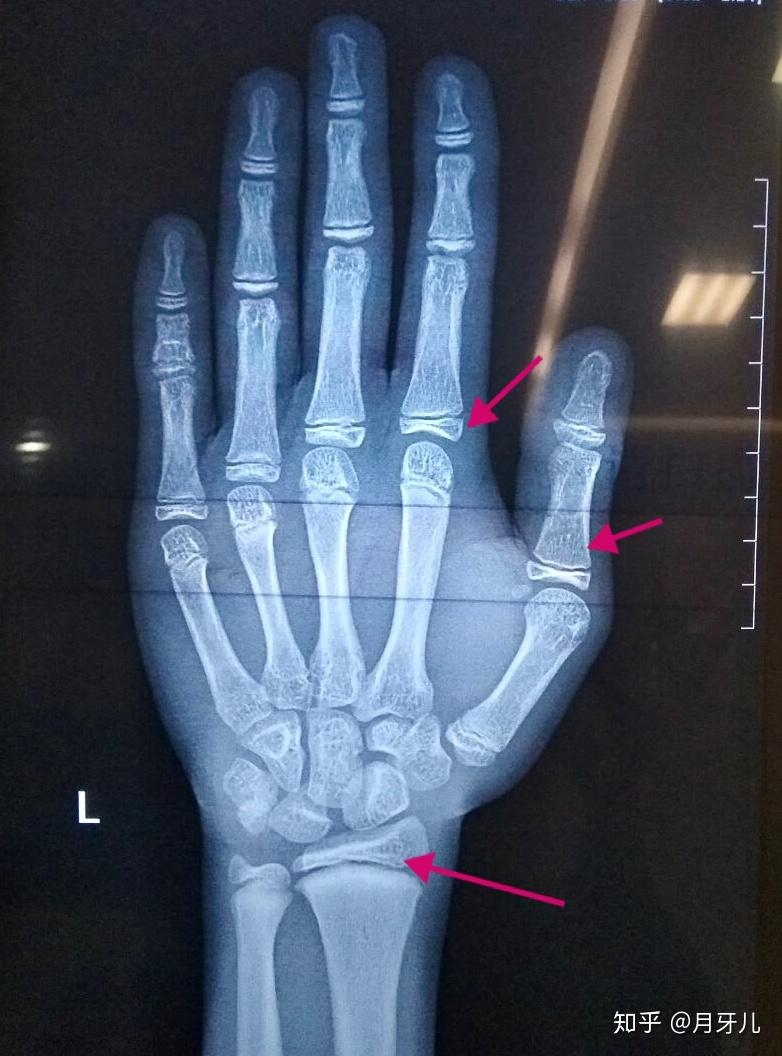

骨骺线算闭合了吗?

如何确诊指骨骨骺早闭?